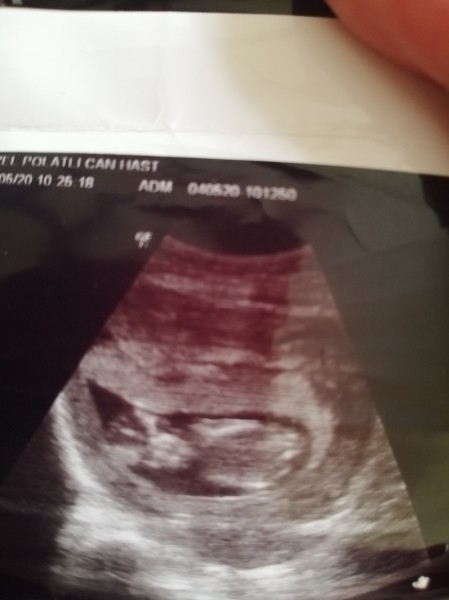

Ultrasondan anlayanlar bakabilir mi bacak arası net

bacak arası görünüyor sanırım ama ben bir şeye benzetemiyorum

Evt erkek cnaim pipi var sol tarafta ba çak arası

Sol taraftaki bacak arası gibime geldi ama bilyorum :) erkek mi.

Bende çözmeye çalışiyorum vallaha doktor %70 erkek demiş

Banada öyle geldi gördüğüm sol taraf ortada kordon değilse erkek gibi.